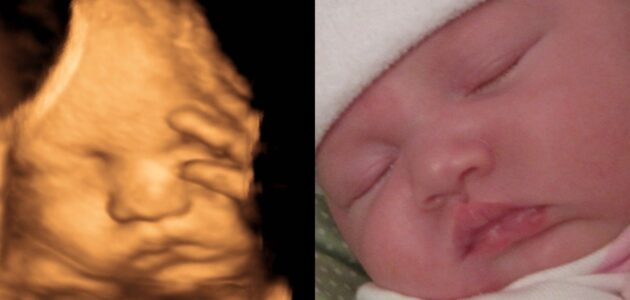

سونوگرافی سه بعدی در دوران بارداری می تواند تصویر سه بعدی و واقعی از چهره جنین را نمایش دهد.

برای دریافت تصاویر خوب، سونوگرافی 3 بعدی بهترین زمان ممکن بین 24 تا 34 هفته است. اما اگر می خواهید یک عکس نزدیک از صورت بگیرید، بهترین زمان برای آن 26 تا 28 هفته است.